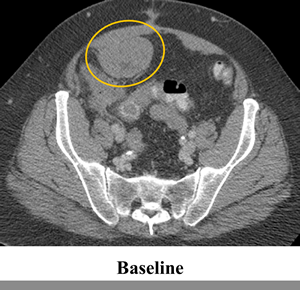

The patient was treated on a phase I trial of dabrafenib at a dose of 150 mg twice daily[10]. The patient’s baseline CT scan demonstrated multiple metastases in the lower abdomen and pelvis, with the largest tumors including a 6.3 cm mass posterior to the bladder and a 6.3 cm mass in the anterior pelvis (Figure 1, Panel A). Using the Response Evaluation Criteria in Solid Tumors (RECIST) 1.0, restaging scans revealed a 14%, 18% and 20% decrease after 6, 15 and 24 weeks of treatment, respectively. Figure 1 Panel B demonstrates response on CT scan at 24 weeks. In addition, the tumor demonstrated a marked decrease in contrast enhancement, a response criteria that has been validated in GIST[12].

Figure 1: Tumor regression of 20% observed in abdominal and pelvic tumors on computerized tomography (CT). CT scan at (a) baseline and after (b) 24 weeks of treatment with BRAF inhibitor dabrafenib (GSK2118436).